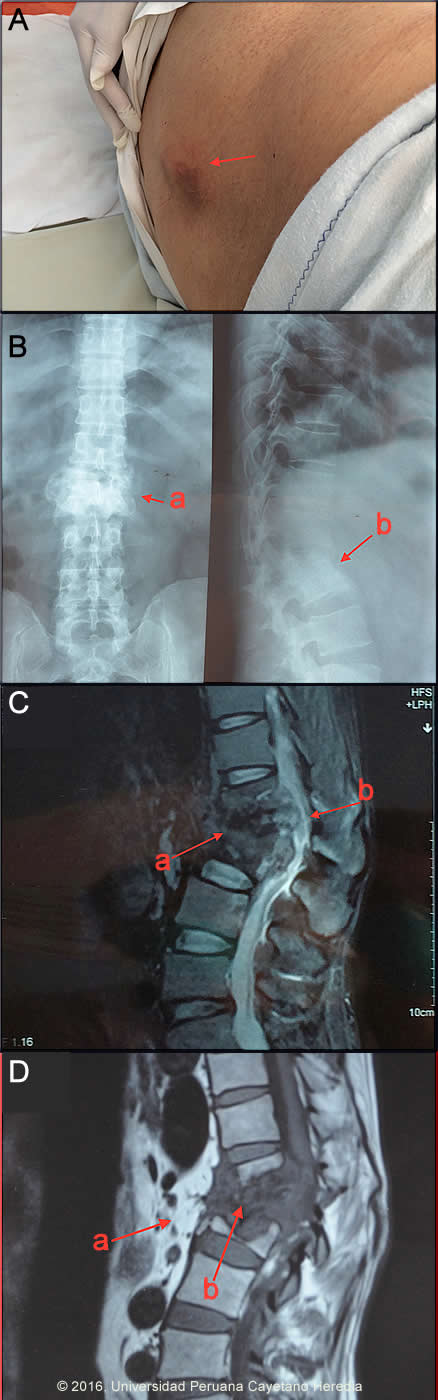

Epidemiology: Born and lives in Paruro (3 hours from Cusco), farmer, with a past medical history of alcoholism, otherwise healthy. No known TB contact. Physical Examination: BP=120/60 HR=76 RR=24 sO2=90%, afebrile. Overall pallor. Chest: bilateral basal rhonchi. Cardiovascular: normal. Abdominal: soft non-tender, no organomegaly. Musculoskeletal: tender, protuberant mass at the level of L1 (Image A). Genitourinary: 2 firm 2X2 cm tender nodules adjacent to left testicle with irregular borders. Neurological: sensory deficit right > left in lower extremities following the L1 distribution (hip girdle and groin area). Motor: decrease of strength in hip flexors (right>left), knee extensor and ankle dorsiflexors (right more than left). Reflexes: Clonus 1+ right ankle. Laboratory Examination (on admission): Hemoglobin: 15.8, Hematocrit: 48%, WBC: 8.87K (77 neutrophils, 23 lymphs 3 monos, 6 eos) Platelets: 218K. BUN: 15, Glucose: 94, Creatinine: 1.1, AST: 9, ALT: 10, Total Protein: 6.9, Albumin: 4, Total Bilirubin: 0.5, Alkaline Phosphatase: 129. HIV negative. Urinalysis: Leukocytes: 25-30, RBC: 65-70. Urine culture for bacteria negative. Renal ultrasound normal. Sputum AFB negative x 3. Chest x-ray normal. Spinal x-ray and MRI shown in Images B, C, D.

Discussion: Urine smear with 2+ AFB; culture positive for MTB susceptible to all 1st line TB drugs. Lumbar spine X-ray (Image B, arrow a) showed L1-L2 collapse with partial destruction of vertebral bodies and total destruction of the intervertebral disc (Image B, arrow b). MRI of the lumbar spine (Image C, T2 weighted) shows a protruding ill-defined heterogeneous mass at L1-L2 (Image C, arrow a) causing posterior spinal cord compression (Image C, arrow b) and without new bone formation. Severe destruction (Image D, T1 weighted) of vertebral bodies L1, L2 (Image D, arrow b) and surrounding tissue inflammation (Image D, arrow a) is seen. In TB spondylitis, the disease process begins in an intervertebral disc and spreads via the anterior ligament to affect the anterior aspects of the adjacent vertebrae. Destruction of the anterior endplates ensues with anterior collapse leading to a wedge deformity seen clinically (Image A), as is well demonstrated in this case, as the spinal deformity known as a gibbus. Tissue obtained by biopsy or needle aspirate and examined histologically and by culture is generally required for diagnosis. AFB smears are usually negative. CT and appropriate neurosurgical experience for invasive diagnosis is not available at this hospital. Complete destruction of vertebral bodies and the intervertebral disc is seen almost exclusively in infectious processes. Salmonella infection or staphylococcal infections may cause spondylitis and paravertebral abscess but concomitant high fever, leukocytosis, and significant systemic illness would be seen. A common feature in these pyogenic vertebral infections is bone remodeling and new bone formation, which was not observed in this patient. Brucellosis, another bacterial cause of spondylitis is not present in this part of Peru as goats are not raised at this altitude; anterior destruction and gibbus is not seen. The spinal lesions of advanced brucellosis include bridging osteophytes, simultaneous with the presence of both osteoblastic lesions and loss of bony mass in the same vertebrae [see Gorgas Case 2001-02]. Malignancy is limited to the vertebral bodies without impinging the intervertebral disc. Tuberculosis is caused by 3 related organisms Mycobacterium tuberculosis, M africanum, and M bovis. Of these, M tuberculosis is by far the most common [Reichman LB, Hershfield ES, editors. Tuberculosis: a comprehensive international approach. New York: Marcel Dekker; 1993]. Vertebral TB is the most common form of skeletal TB [Spine. 1997; 22(15):1791-1797], whereas male genital TB is an uncommon form of extrapulmonary TB [Urol Clin North Am. 2003;30(1):111- 121]. The initial route of entry of M. tuberculosis is usually the respiratory tract, followed by hematogenous dissemination. Secondary hematogenous seeding can occur from a silent focus elsewhere in the body (eg gut, kidney, and tonsil). Skeletal tuberculosis is thought to result from hematogenous dissemination from a primary site and occurs 6 months to 3 years after primary infection; but cases associated with relapsing disease have been reported. Spinal TB accounts for more than 50% of all skeletal cases with 50% involving the thoracic spine, 25% cervical and 25% the lumbar spine [WJ Bone Joint Surg Am. 1996 Feb; 78(2):288-98]. Pott’s (named after first description of TB spondylitis by the British surgeon Sir Percivall Pott, 1714-1788) disease usually presents with chronic back pain that is initially non-specific. Pain increasing in severity over weeks to months is seen in association with muscle spasm. Constitutional symptoms (fever, weight loss) are present less than 40% of cases [Int Orthop. 2012 Feb;36(2):221-31, J Neurosurg. 1995 Aug;83(2):243-7]. Cord compression with muscle weakness and loss of bladder and bowel control is the most serious complication and occurs in up to 30% of patients. Genitourinary TB (GU TB) is insidious, usually presenting with malaise and lower urinary tract symptoms including dysuria and hematuria. [Am J Respir Crit Care Med. 2000 Apr;161(4 Pt 1):1376-95, Am J Med. 1977 Sep;63(3):410-20, Medicine (Baltimore). 1974 Sep;53(5):377-90] Systemic symptoms are rare. Pyuria and hematuria are present in more than 90% of cases and serum creatinine is usually normal. Ureteral stricture could occur and may cause obstructive uropathy. It could also cause chronic epididymitis or prostatitis and infertility if seminal vesicles and ejaculatory ducts in men and fallopian tube in women are involved. The diagnosis of GU TB is by demonstration of the bacilli in urine in patient with dysuria, sterile pyuria, hematuria and/or radiological findings suggestive of TB. Medical therapy of Pott’s disease is with standard regimens of anti-TB drugs for at least 9 - 12 months, but more prolonged therapy is recommended in patients with extensive bone destruction and paravertebral extension. In Pott’s disease, controversy exists as to the need for any reconstructive surgical intervention or fusion procedure in patients without neurologic deficit, with many published studies either way. None of the studies of shorter course chemotherapy have included enough patients with Pott’s disease to make any conclusions possible. Patients with acute neurologic deficits within the previous 12-24 hours should definitely have surgery. With longer standing neurologic deficit there is not well-controlled data to show better outcomes with surgery, but where neurosurgical intervention is accessible it is often undertaken in conjunction with medical therapy. Steroids should be considered for very severe paraplegia, especially in the acute stage. Recommendations for a surgical procedure include (1)Patients with spinal disease and advanced neurological déficits, (2)Patients with spinal disease and worsening neurological deficits progressing while on appropriate therapy, (3)Patients with spinal disease and kyphosis >40 degrees at the time of presentation and (4)Patients with a cold abscess in the chest wall. Medical therapy for GU TB is generally the same as that for pulmonary TB and 6 months duration is successful in eradicating drug susceptible TB. Upper urinary tract obstruction during treatment might occur with significant worsening during the first weeks of treatment due to inflammation followed by fibrosis and consequent obstruction of collecting system. Aside from decompression other surgical interventions should be delayed for at least 4 weeks after initiation of drug therapy. Our patient has been started on the standard 4-drug initiation regimen of daily INH, rifampin, ethambutol, and pyrazinamide in addition to dexamethasone for the cord compression syndrome. Surgical evaluation and discussion of approaches to further spine stabilization is ongoing. |